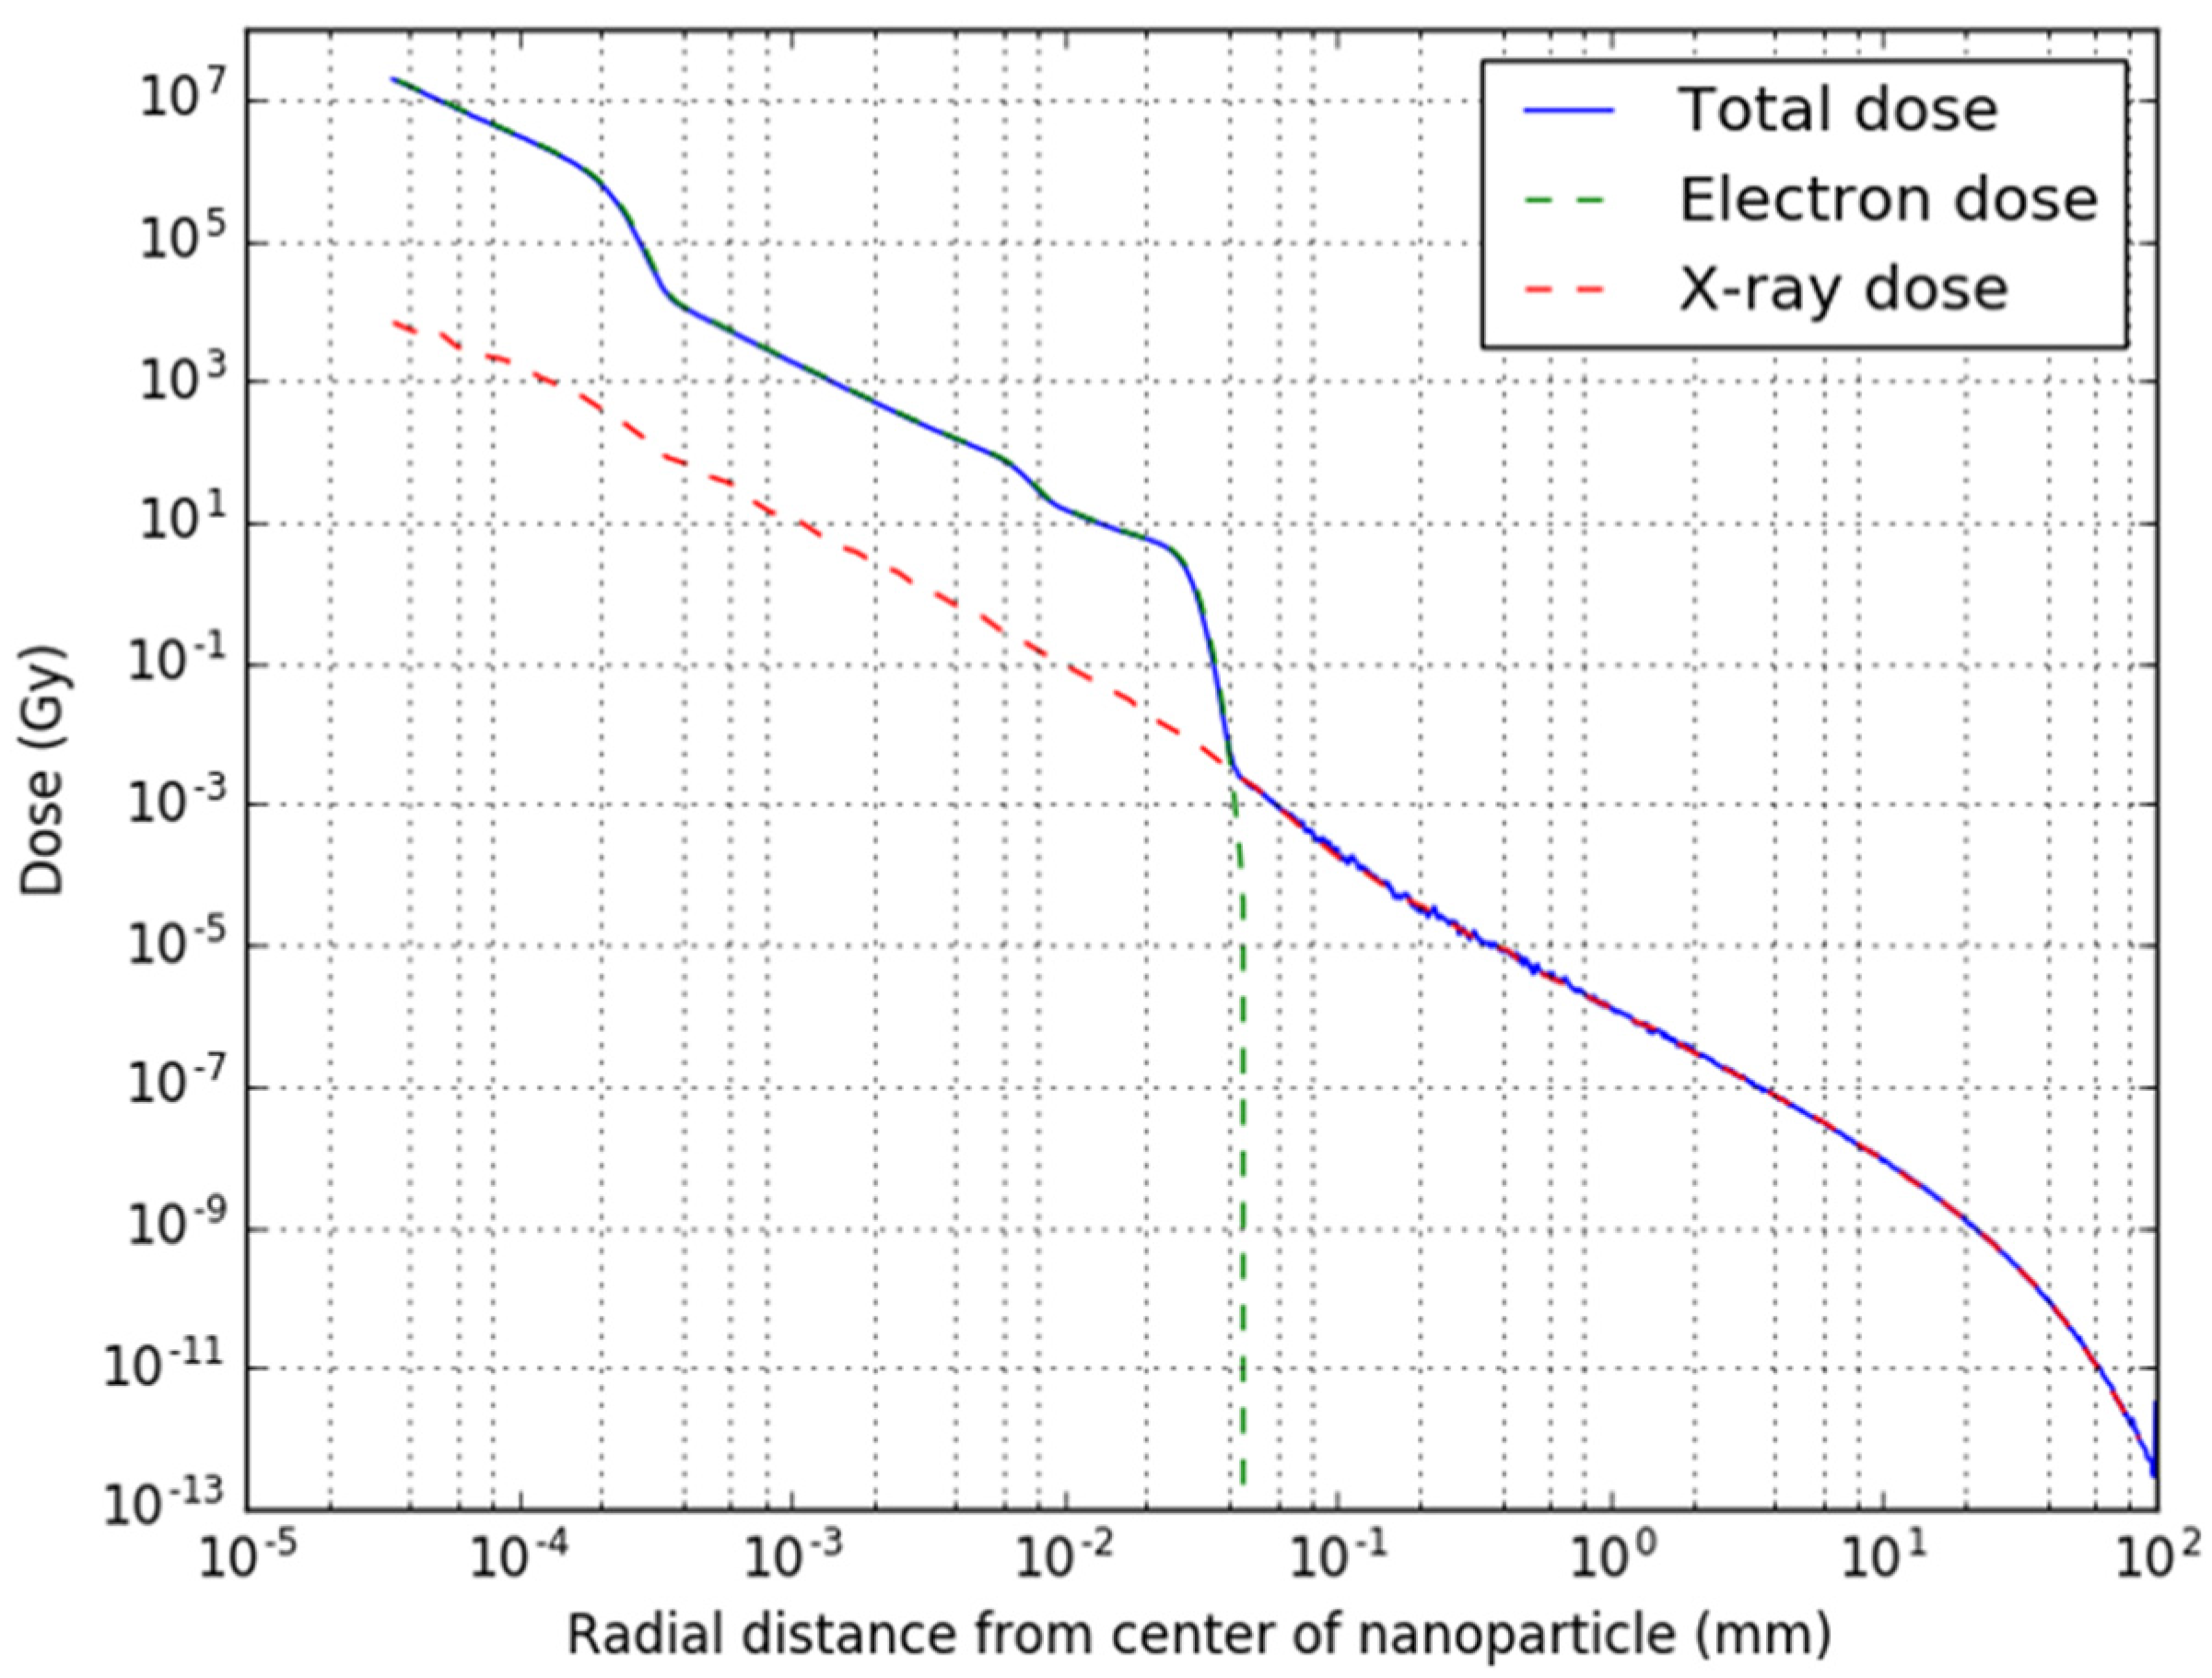

2.2. Single Nanoparticle Simulations

3.1. Single Nanoparticle Energy Spectra

3.2. Radioactive Magnetic Nanoparticle (RMNP) Seed